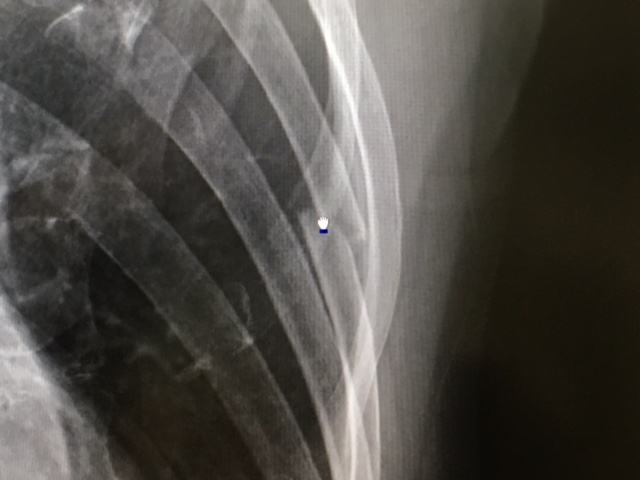

↓こちら、1ヶ月後。

ポッキリはポッキリのままですが、その周りにモワッと「仮骨」の影が・・・。そして、隣の4番目の右側にもチラッと「仮骨」の影が。この頃から、日常生活においてはほぼ痛みはなし。でも、まだあまり激しい動きをしないように、ソロソロと過ごす(苦笑)。